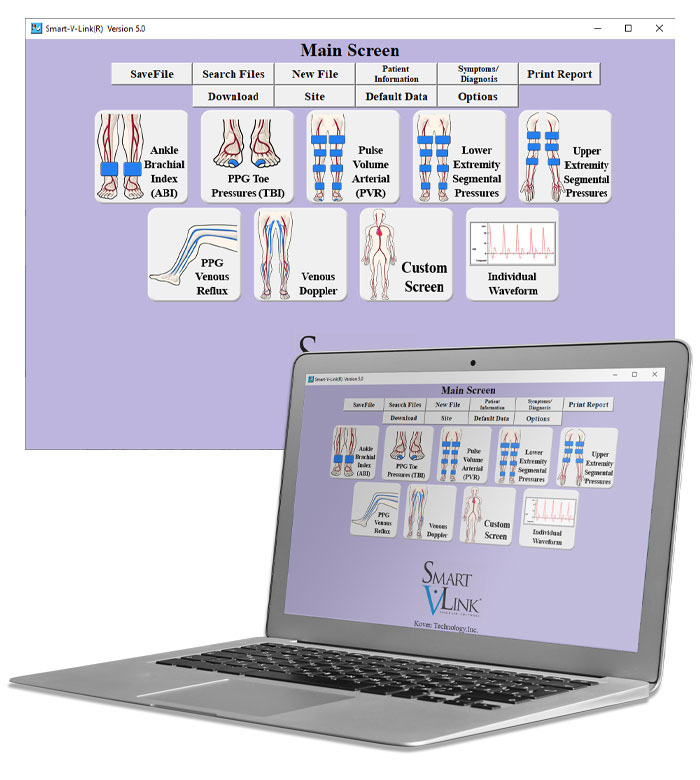

what is a pvr test